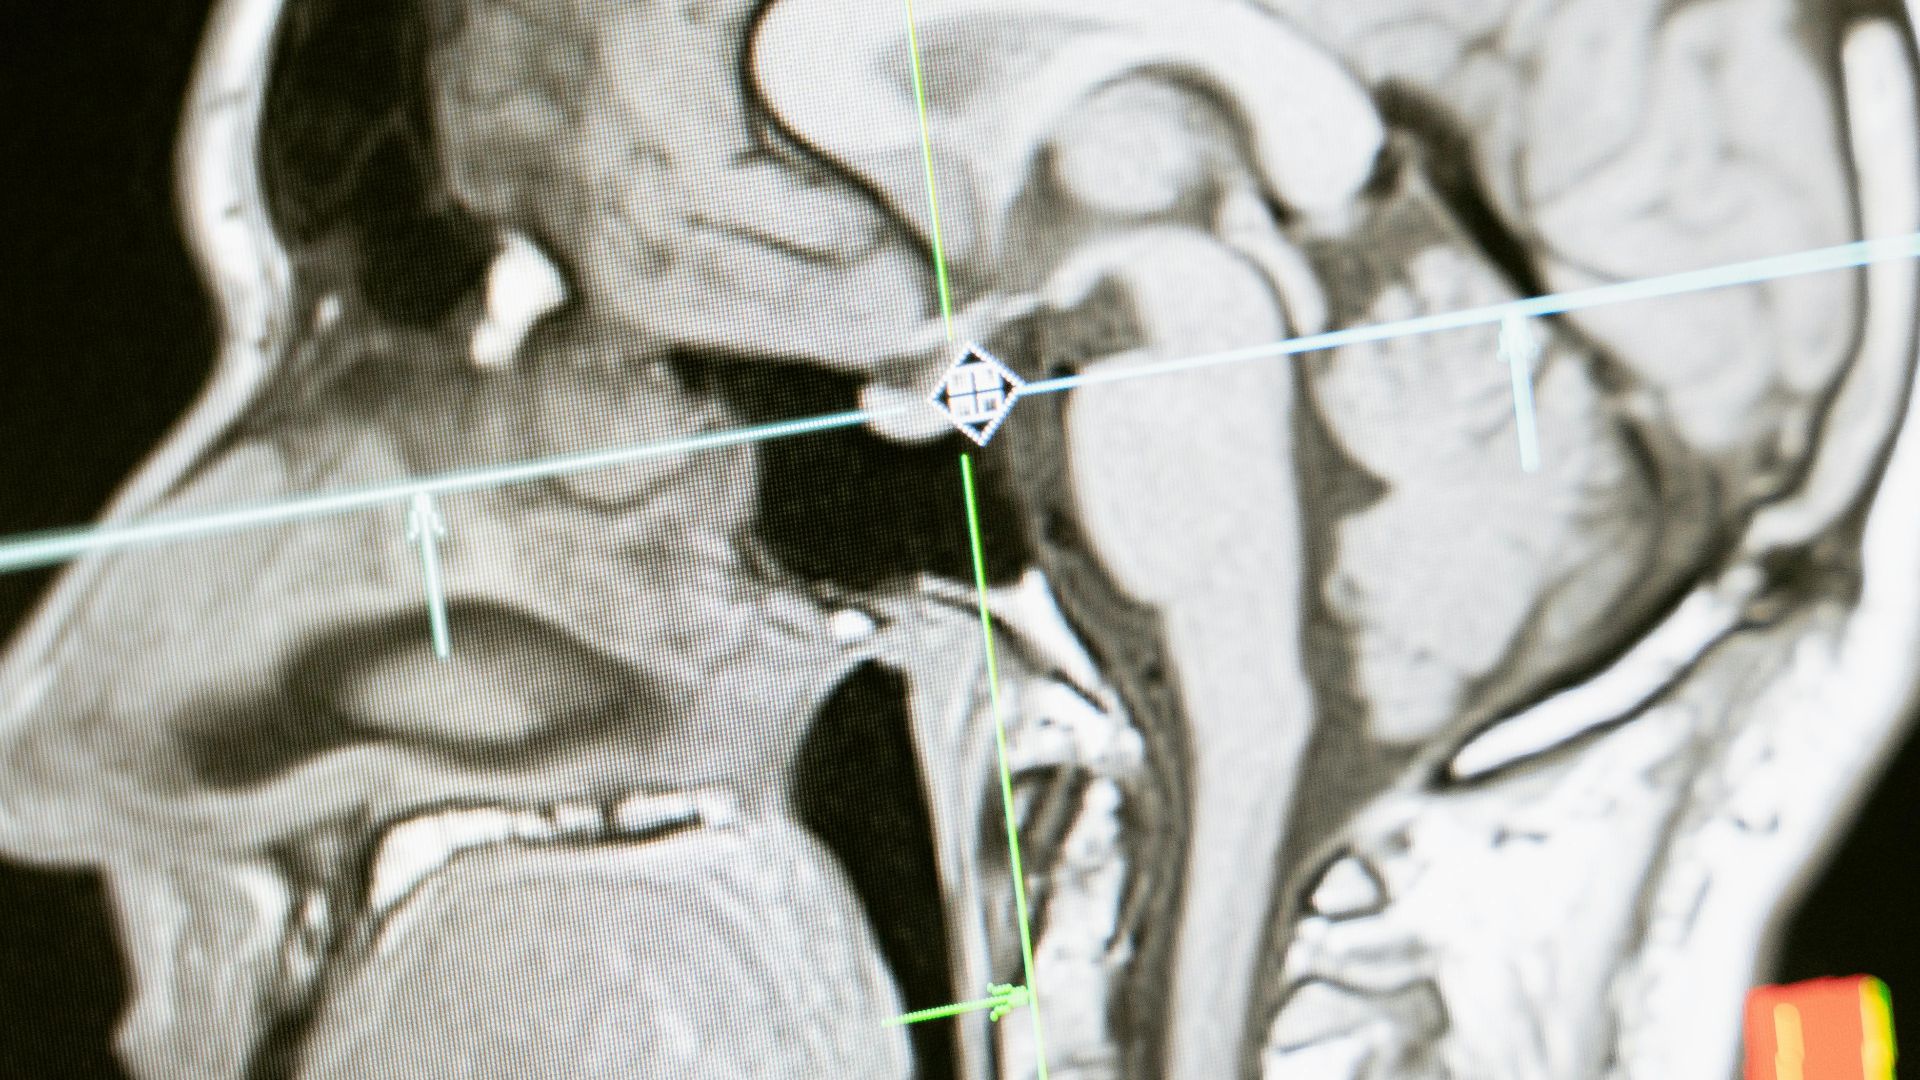

13. Détection de la maladie

Les algorithmes analysent les images médicales à la recherche de tumeurs ou d’anomalies qui pourraient échapper aux médecins et les comparent à l’ensemble de la littérature médicale. Ils mettent en évidence les points suspects en quelques secondes. Ce n’est pas infaillible, mais c’est d’une précision redoutable.